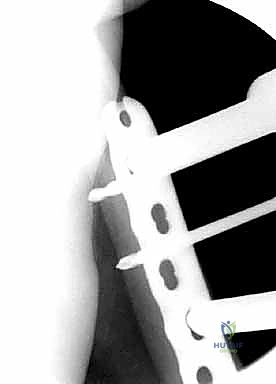

المرحلة الرابعة: التثبيت النهائي بالشرائح والمسامير (Fixation)

يتم استخدام "شرائح الإغلاق التشريحية" (Anatomical Locking Plates) المصنوعة من التيتانيوم عالي الجودة. هذه الشرائح مصممة خصيصاً لتأخذ شكل الجزء السفلي من عظم الفخذ. يتم تمرير الشريحة أسفل العضلات وتثبيتها بمسامير تغلق داخل الشريحة نفسها (Locking Screws)، مما يوفر ثباتاً ميكانيكياً هائلاً، حتى في حالات العظام الهشة.

في بعض الحالات المعقدة جداً، قد يتطلب الأمر استخدام شريحتين (Dual Plating) لضمان عدم تحرك الكسر أثناء فترة التعافي.